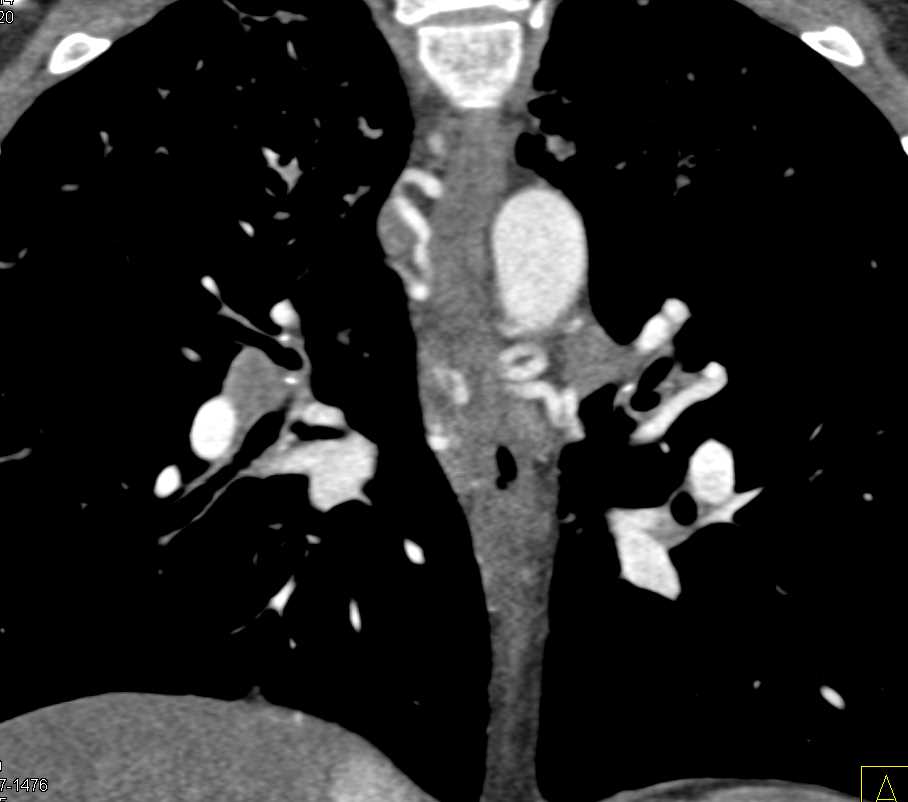

If you know someone who has a smoking history, tell them to ask their doctor and see if lung cancer screening is right for them! Quitting < 15 years is not required to qualify for screening anymore. #LungCancerAwareness #LungCancerAwarenessMonth Society of Thoracic Radiology #chestrad